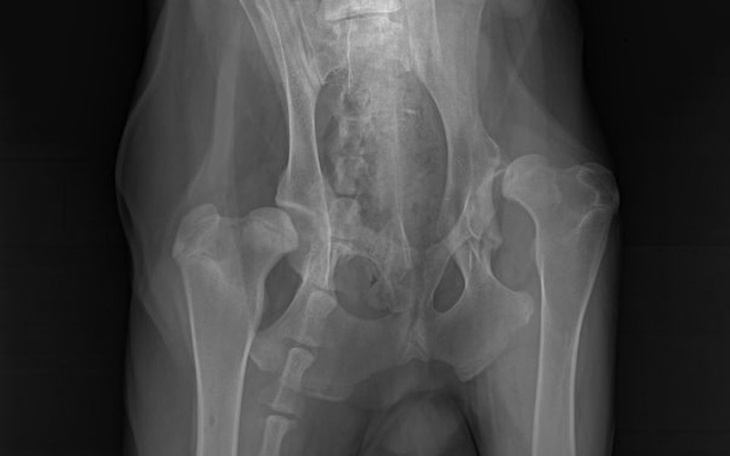

Obustronna dysplazja stawów biodrowych, masywna deformacja kości, przebudowa stawu łokciowego lewego wtórna do dysplazji stawu łokciowego, zwichnięte biodro, prawe na granicy nadwichnięcia, stan zapalny, duża bolesność.

- Resekcja głowy i szyi kości udowej P (ok. 1500 zł) + dartroplastyka (3500 zł).

- Protezowanie stawu biodrowego L (10.000-12.000 zł jedna strona). Jeśli pogorszy się stan P, protezowanie obu.